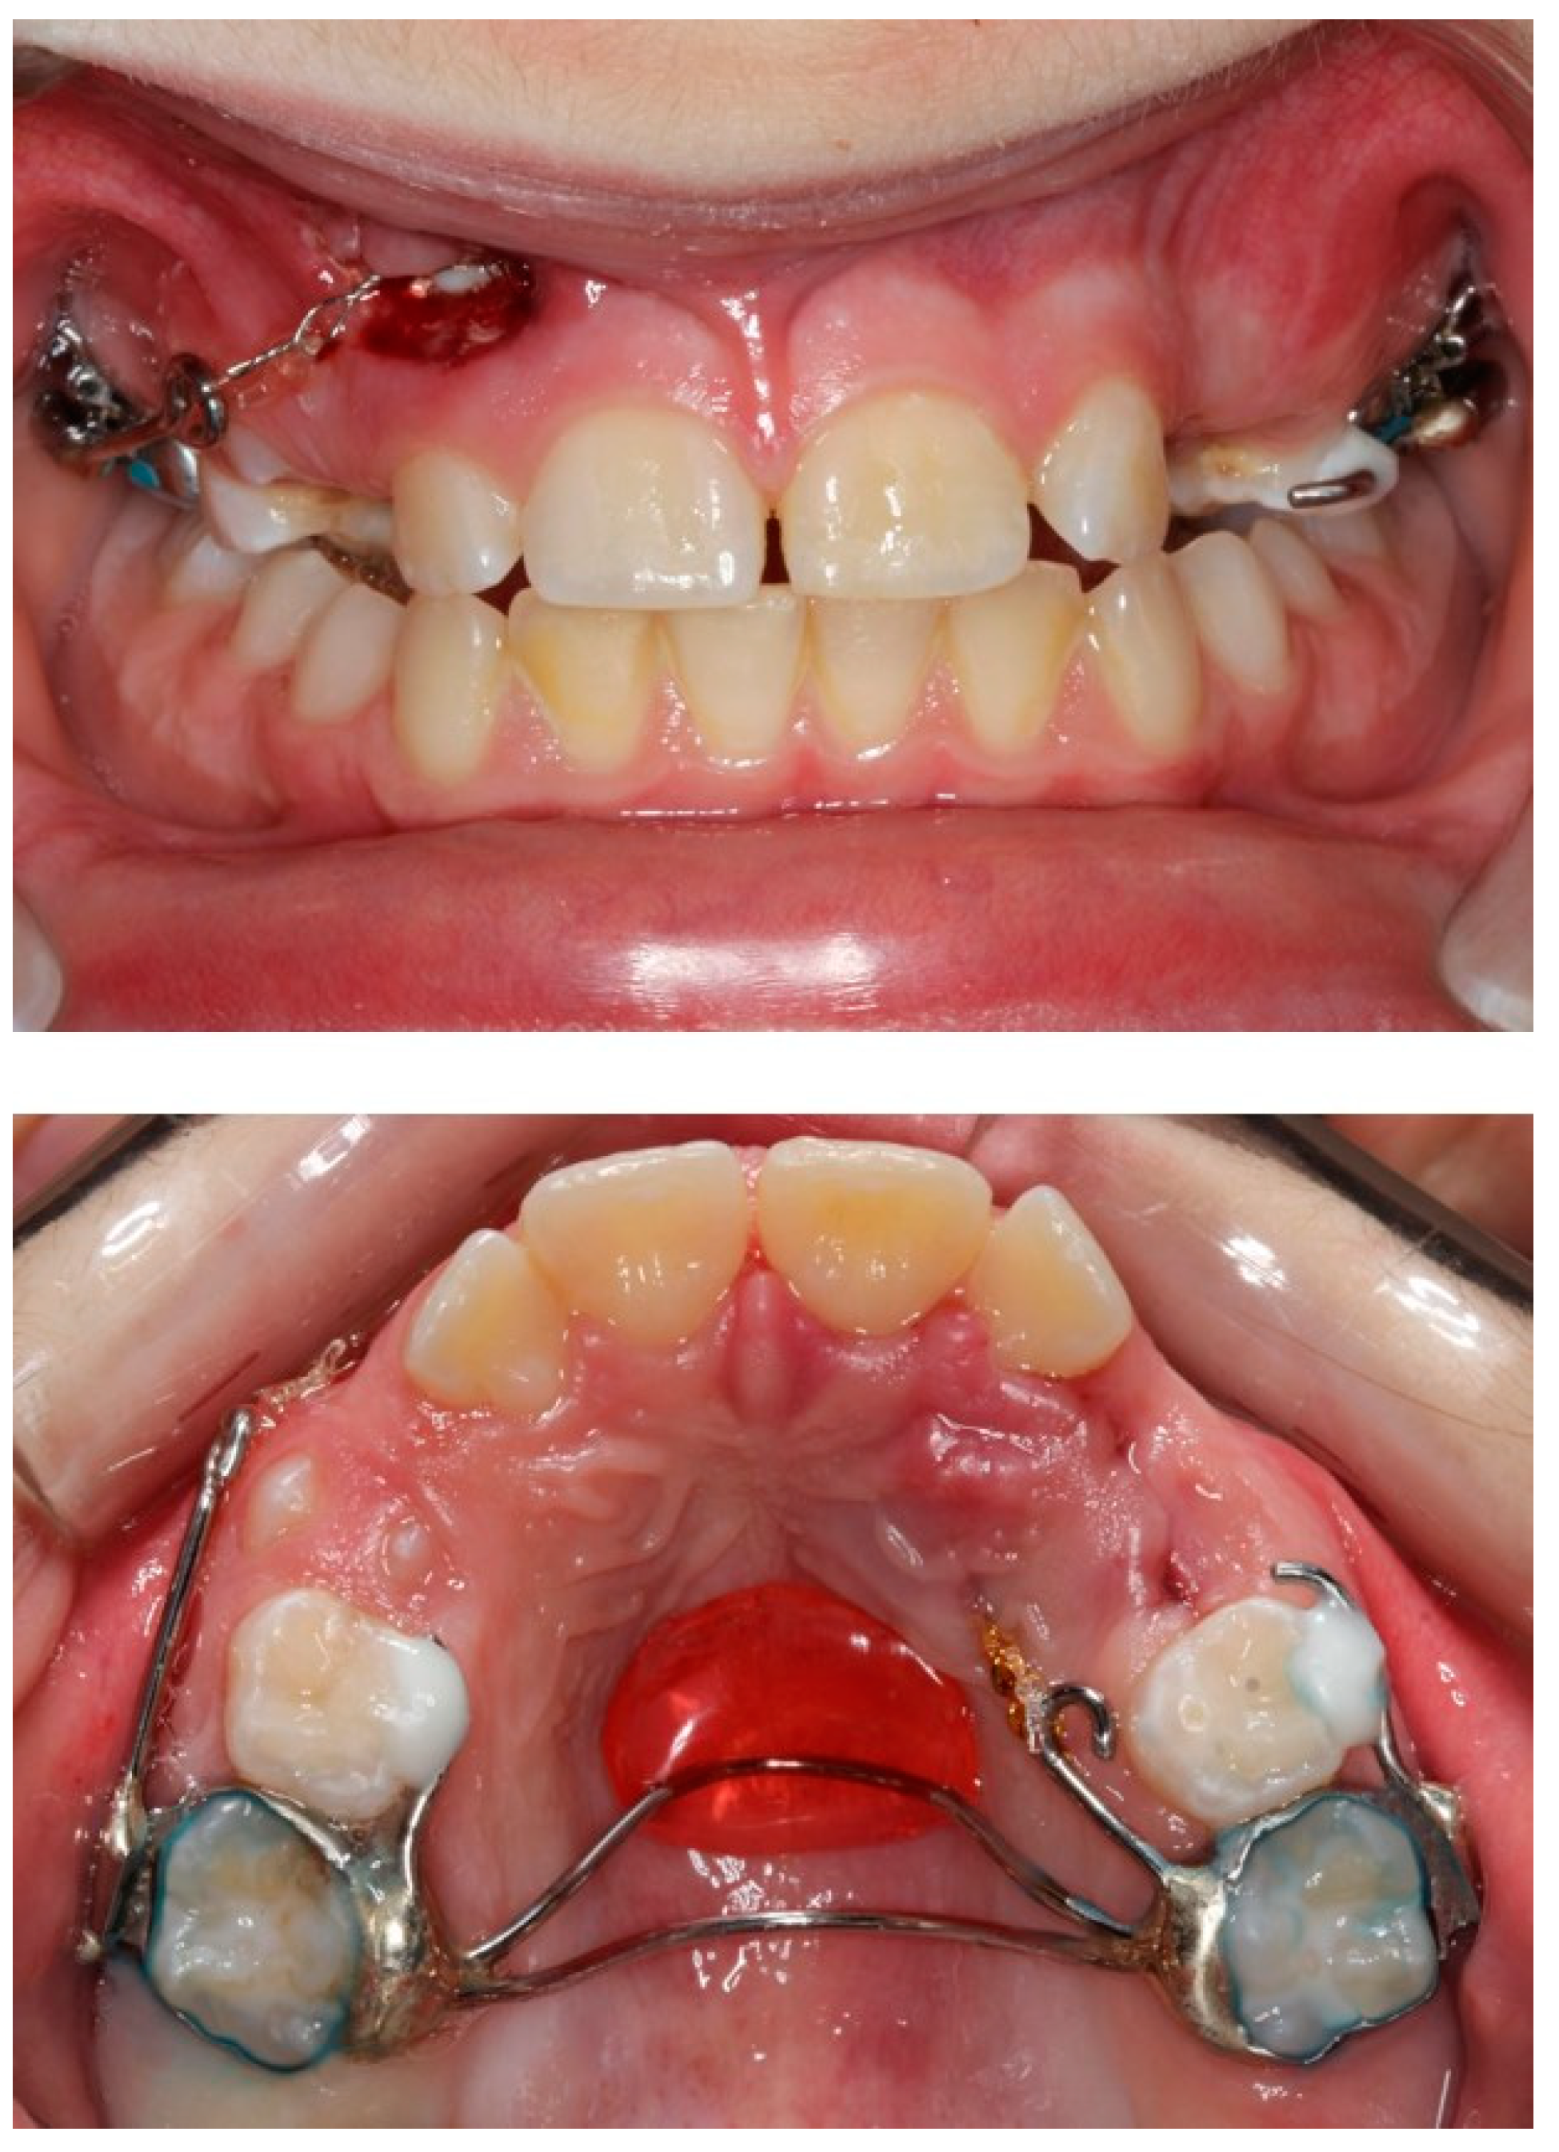

The custom-made trans-palatal arch used for the traction of the impacted canines.

Progress photographs of the custom-made trans-palatal arch used for the traction of the impacted canines.

The orthodontic treatment was initiated with the canine exposure (Figure 5) and traction with light forces using a custom-made trans-palatal arch for anchorage purposes (Figure 6 and Figure 7). An open surgical technique (apically positioned flap) was used to expose the labially positioned right canine and a closed technique for the left, which was positioned palatally. Sectional mechanics were applied during treatment until the eruption of all permanent teeth (Figure 8). The upper lateral incisors were extracted after the successful eruption of the impacted canines and for aesthetic reasons. Subsequently, comprehensive orthodontic treatment was performed using fixed 0.018-inch-slot edgewise appliances. A lower lingual arch was placed to preserve the leeway space thus helping with the lower crowing. The progression of the archwire sequence was from 0.014-inch nickel-titanium to 0.016-inch Australian archwires. Class III light elastic forces were used bilaterally to help with space closure on the upper arch.

The dental age and the adverse tooth prognosis in this patient necessitated the use of a custom made trans-palatal arch for the traction of the canines. This arch was bonded on the permanent first molars, as well as the palatal and buccal surfaces of the right and left deciduous second molars, respectively. The appliance was further stabilized on the hard palate mucosa with an acrylic button. This design allowed the even distribution of the reciprocal forces during the canine traction on the aforementioned structures.